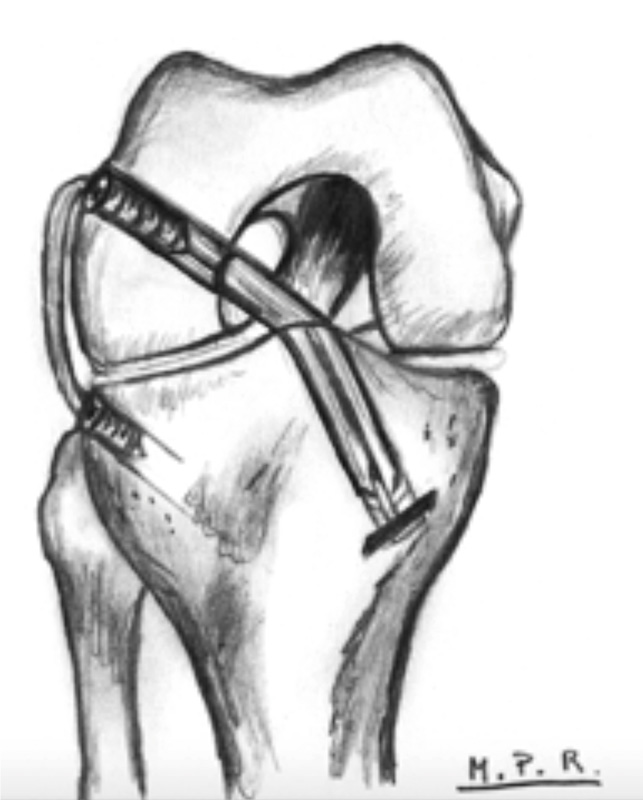

Hoy en día, con el objetivo de controlar este pivot shift residual, se está asociando en algunos pacientes técnicas de reconstrucción de las estructuras anterolaterales asociadas al LCA, usando diferentes estructuras como son la fascia lata(34), tendones de la pata de ganso(35), aloinjertos(36) e incluso injertos artificiales(37)(Figura 5).

Para conseguir una reconstrucción exitosa, la posición de la plastia es fundamental(23)(Figura 6). La malposición de los túneles y los cambios en la longitud con respecto al grado de flexión de la rodilla pueden llevar a un aumento de tensión en el compartimento lateral y la plastia, lo que degenera en un fallo de la plastia y degeneración en el compartimento lateral(19,23).

Figura 5. Reconstrucción del ligamento cruzado anterior (LCA) asociada a refuerzo lateral extraarticular.

Figura 6. Imagen quirúrgica de una tenodesis extraarticular lateral de tipo Lemaire modificada. Nótese la presencia de los hilos de tracción de la plastia intraarticular anatómica del ligamento cruzado anterior (LCA).